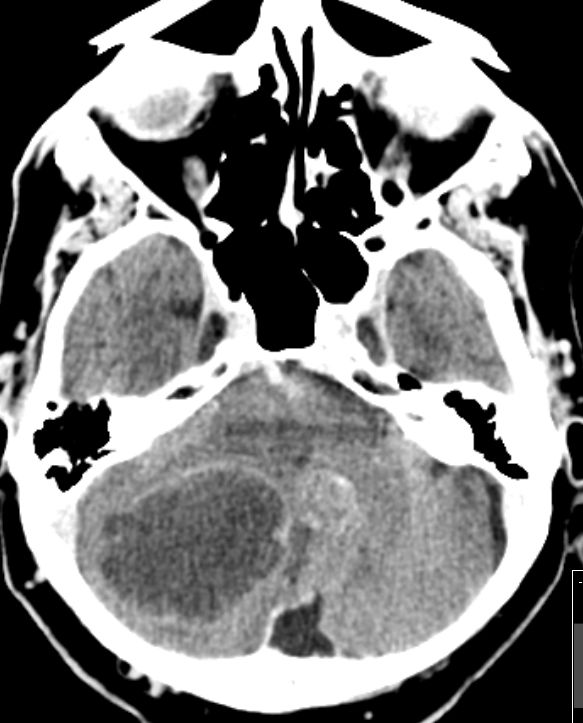

Hirnmetastasen 72-jähriger Mann, der 1 Jahr nach einem Caecumkarzinom cT3 cNo G3, eine Kleinhirnmetastase entwickelte. Abdomen und Leber frei.

CT nach KM-Gabe und MRT:

Hirnmetastasen CT nach KM-Gabe: Hirnmetastase